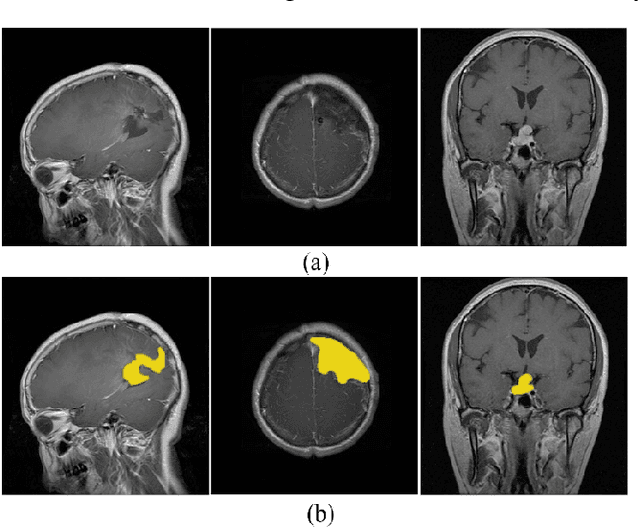

Abstract:Intracranial tumors are groups of cells that usually grow uncontrollably. One out of four cancer deaths is due to brain tumors. Early detection and evaluation of brain tumors is an essential preventive medical step that is performed by magnetic resonance imaging (MRI). Many segmentation techniques exist for this purpose. Low segmentation accuracy is the main drawback of existing methods. In this paper, we use a deep learning method to boost the accuracy of tumor segmentation in MR images. Cascade approach is used with multiple scales of images to induce both local and global views and help the network to reach higher accuracies. Our experimental results show that using multiple scales and the utilization of two cascade networks is advantageous.

Abstract:Recently deep learning has been playing a major role in the field of computer vision. One of its applications is the reduction of human judgment in the diagnosis of diseases. Especially, brain tumor diagnosis requires high accuracy, where minute errors in judgment may lead to disaster. For this reason, brain tumor segmentation is an important challenge for medical purposes. Currently several methods exist for tumor segmentation but they all lack high accuracy. Here we present a solution for brain tumor segmenting by using deep learning. In this work, we studied different angles of brain MR images and applied different networks for segmentation. The effect of using separate networks for segmentation of MR images is evaluated by comparing the results with a single network. Experimental evaluations of the networks show that Dice score of 0.73 is achieved for a single network and 0.79 in obtained for multiple networks.